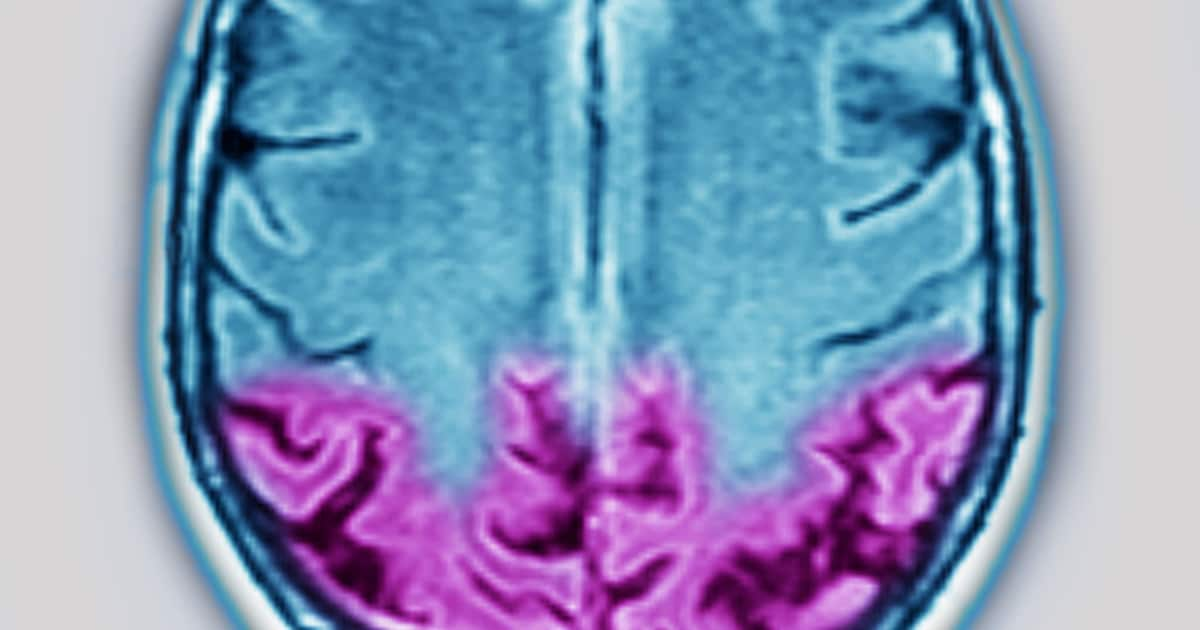

Ataxie est un terme médical général désignant les troubles de la coordination des mouvements et de l’équilibre résultant de lésions ou d’un dysfonctionnement du cervelet, de la moelle épinière, des nerfs périphériques ou des structures associées du système nerveux central.

Les causes de l’ataxie sont très diverses et peuvent être divisées en formes héréditaires (génétiques) et acquises, ces dernières pouvant souvent être traitées. Les variantes héréditaires telles que l’ataxie de Friedreich (forme la plus courante chez les adolescents) résultent d’anomalies génétiques entraînant des carences en protéines ou des dépôts toxiques dans le cervelet et la moelle épinière, souvent associées à des problèmes cardiaques ou de diabète. Les ataxies acquises résultent d’accidents vasculaires cérébraux, de tumeurs ou d’inflammations du cervelet, de maladies démyélinisantes telles que la sclérose en plaques, d’infections (par exemple la maladie de Lyme transmise par les tiques), d’un abus chronique d’alcool, de carences en vitamines (en particulier B1 ou E), de toxines (par exemple la chimiothérapie) ou de processus auto-immuns. Des formes rares comme l’ataxie-télangiectasie touchent les enfants et sont associées à un déficit immunitaire et à un risque de cancer. Une localisation précise – cérébelleuse, sensorielle ou vestibulaire – détermine la gravité des symptômes.